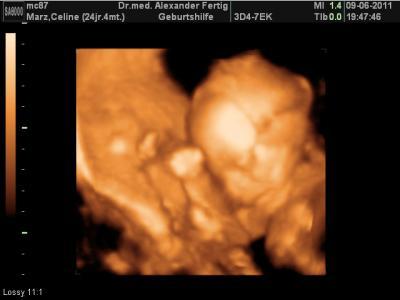

Hallo und Ihr Lieben, Urinwerte waren o.B., Blutdruck: 127/83 Nun zum US: Baby ist nun ca. 26cm groß und wiegt ca. 300g, KU= 18cm Keine Wassereinlagerungen im Kopf, Organe sind alle angelegt, das Herzchen hat 4 Kammern, Rücken ist geschlossen, Wirbelsäule ist normal entwickelt. Oberschenkelknochen haben normale gr. *LOL* als er den Bauch des Baby´s vermessen hat meinte er der Würm wäre gut genährt . Hmm, fällt mir noch was ein Ach ja, wir konnten aus den 95% ein 100% Mädchen machen Hab jetzt gegen meine seitenstechen ähnliche Beschwerden im Unterleib ne Packung 400mg Magnesium, 2x tägl. empfohlen bekommen. Wären seiner meinung nach die Mutterbänder...baaahhh so arg?? Naja, bin ja beruhigt wenns nur das ist! Über den Zuckertest haben wir gespr., machen wir beim übernächsten mal. Der nächste Termin findet schon in 2 1/2 Wochen statt, da mein Gyn. 14 Tage in Urlaub geht. Ich hab damit keine Probleme ^^ Es folg ein Bildchen... (Bilder sind diesmal nicht so schön geworden )

Bild zu Mein Bericht v. gestrigen Gyn.-Termin! - Forum für Oktober - Mamis